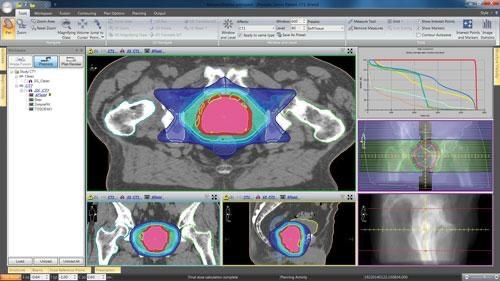

前列腺癌放疗的靶区设计